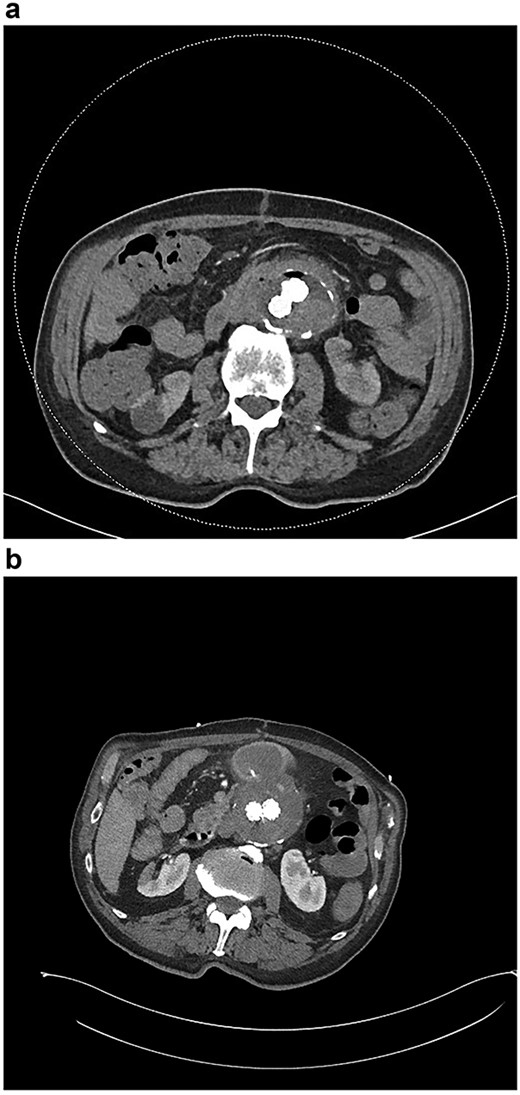

(a) CT angiogram demonstrating new gas in the aneurysmal sac 6 weeks post-repair; (b) CT angiogram just prior to the second repair, demonstrating ongoing endoleak and continuity of the duodenum and sac; part of the duodenal clip is visible.

Six months after the index presentation, a secondary AEF was diagnosed. The patient presented similarly with syncope after massive hematemesis and a 5-day history of melena. CT angiography again demonstrated the type 2 endoleak, with active contrast extravasation into the third part of the duodenum (Fig. 3b). Once resuscitated, the patient was treated with an open explant of the stent, repair of the duodenum and bilateral axillofemoral bypass. Residual anchors from the previous EVAR remained in situ. Over two years later, he remains active and independent despite his incisional hernia, playing golf multiple times per week. His eGFR is 34 ml/minute/1.73m2. He remains on long-term anti-microbial suppression.